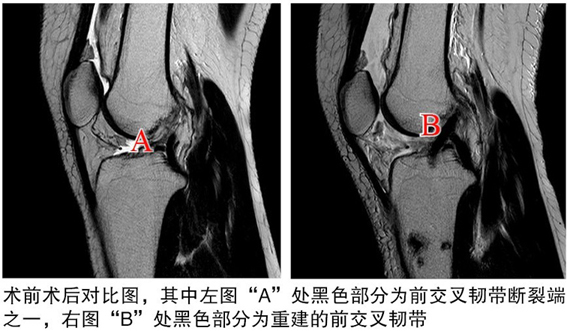

術(shù)后

關(guān)節(jié)鏡下見(jiàn)重建的前交叉韌帶